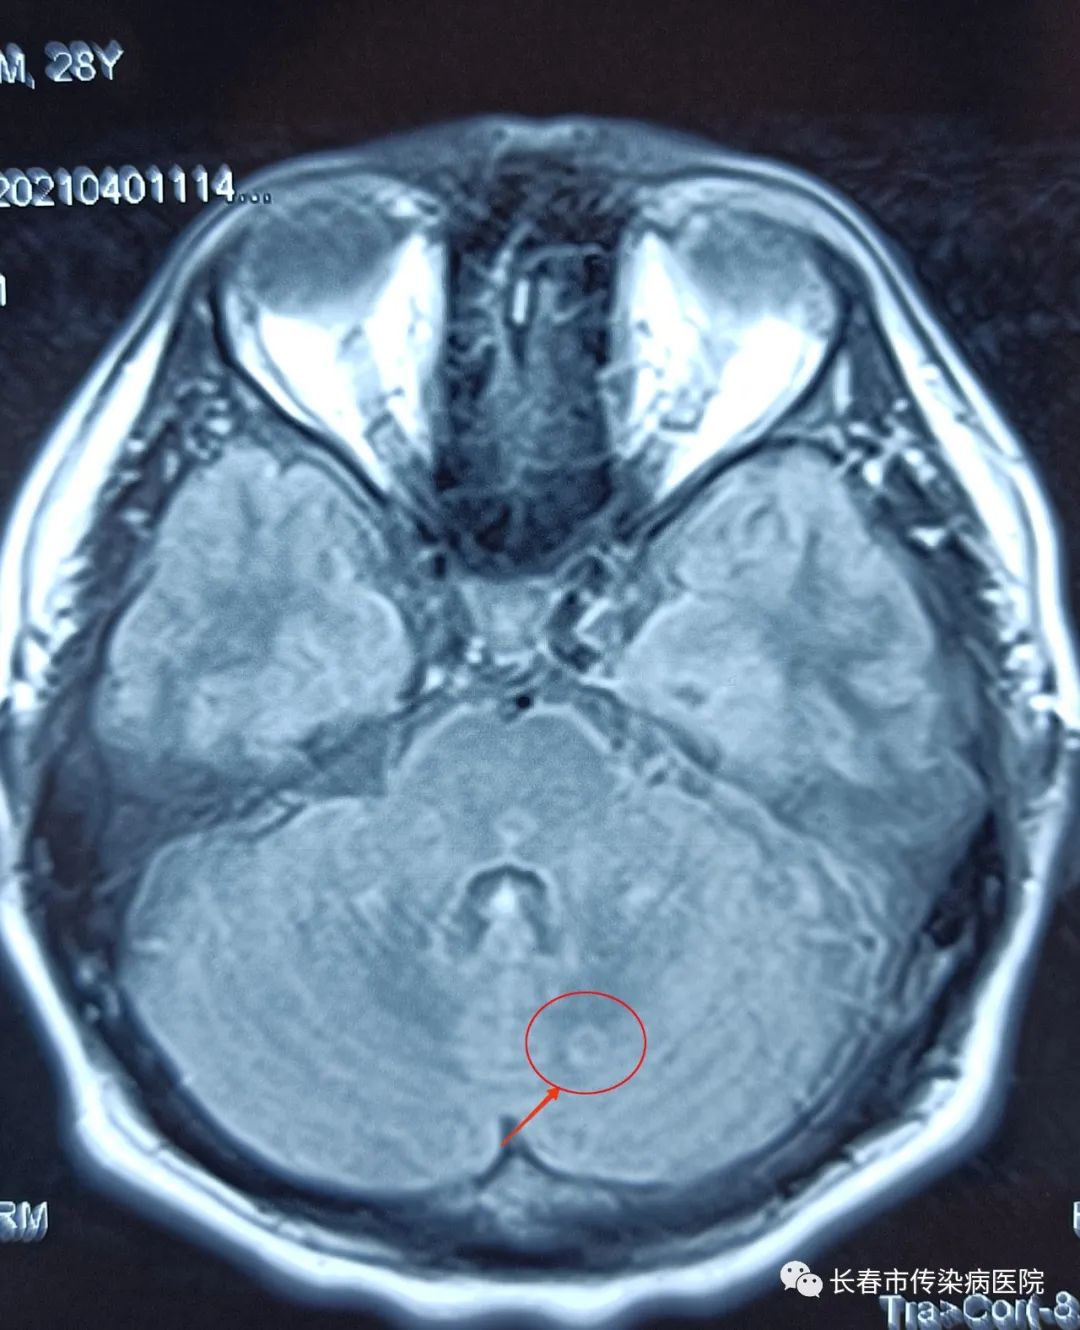

头部MRI(吉大二院,2021-04-1):右侧颞叶,右侧枕叶,双侧小脑半球见类圆形等T1、长T2、Flair呈高信号的异常信号影。

3、脑脊液细胞学(见上图)

结核性脑膜脑炎,后期头部核磁增强扫描亦证实颅内病灶符合结核性脑膜脑炎改变。